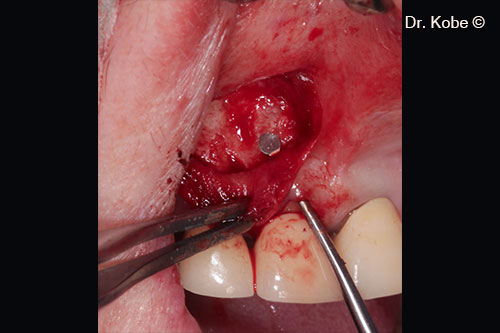

Access to the defect